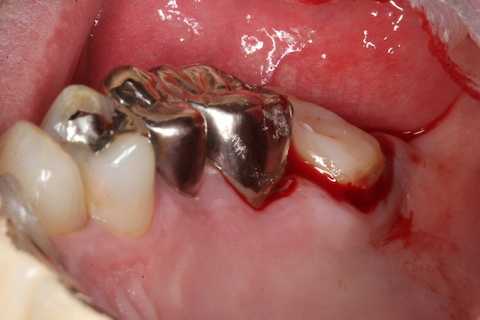

40代男性、左上7、歯根破折

今日は再建した歯を抜歯窩に挿入して固定するまで。

固定という処置は必ずしないといけないのだが、昔の教科書では強固な固定ではなく縫合糸でゆるゆるの歯肉固定だった。これでは生着の確率は下がる。再植歯の排出機転が働いてしまいやすい。

スーパーボンドとCRによる歯牙固定が良いと思う。

また異物の混入等を防ぐための包帯は必要だ。腫脹が治ると隙間ができた食渣等で汚染されるので、1週間後には除去した方が良い。ここではデュラシールを使っている。

隣接歯の接着面には接着性を良くするためにグルーブを形成し、あらかじめスーパーボンドを流しておく。